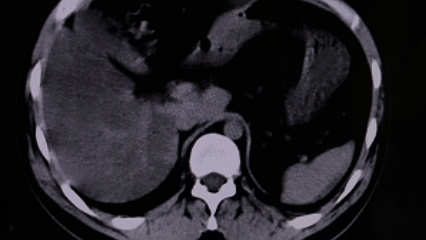

近日,我院泌尿外科团队成功为一名30岁男性患者实施了经皮肾镜下左肾结石碎石取石术。该患者病情复杂,同时患有左肾结石伴有积水和感染、双侧肾囊肿、髓质海绵肾以及乙型病毒性肝炎,手术难度与风险较高。在医护团队的精心施治与细致照护下,患者手术顺利,术后恢复良好,目前已康复出院。

经过系统治疗,患者左侧腰部疼痛症状消失,术后复查显示左肾结石已基本清除,肾功能逐步恢复,目前已顺利出院并进入后续随访阶段。